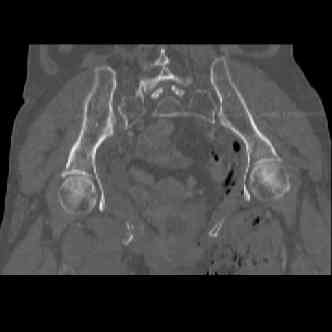

attached are images of a 70 year old female after peds versus car. her own car ran her over.

injuries are limited to the pelvis. left rami open and visible in a 10cm vertical laceration just lateral to left labia majora. wound is grossly clean. no vaginal and no urinary issues. CT scan shows widening of both SI joints anteriorly but I think this is vertically stable pattern.

attached are several CT cuts. please let me know if you need more. the CT is pre-pelvic ex-fix placement.